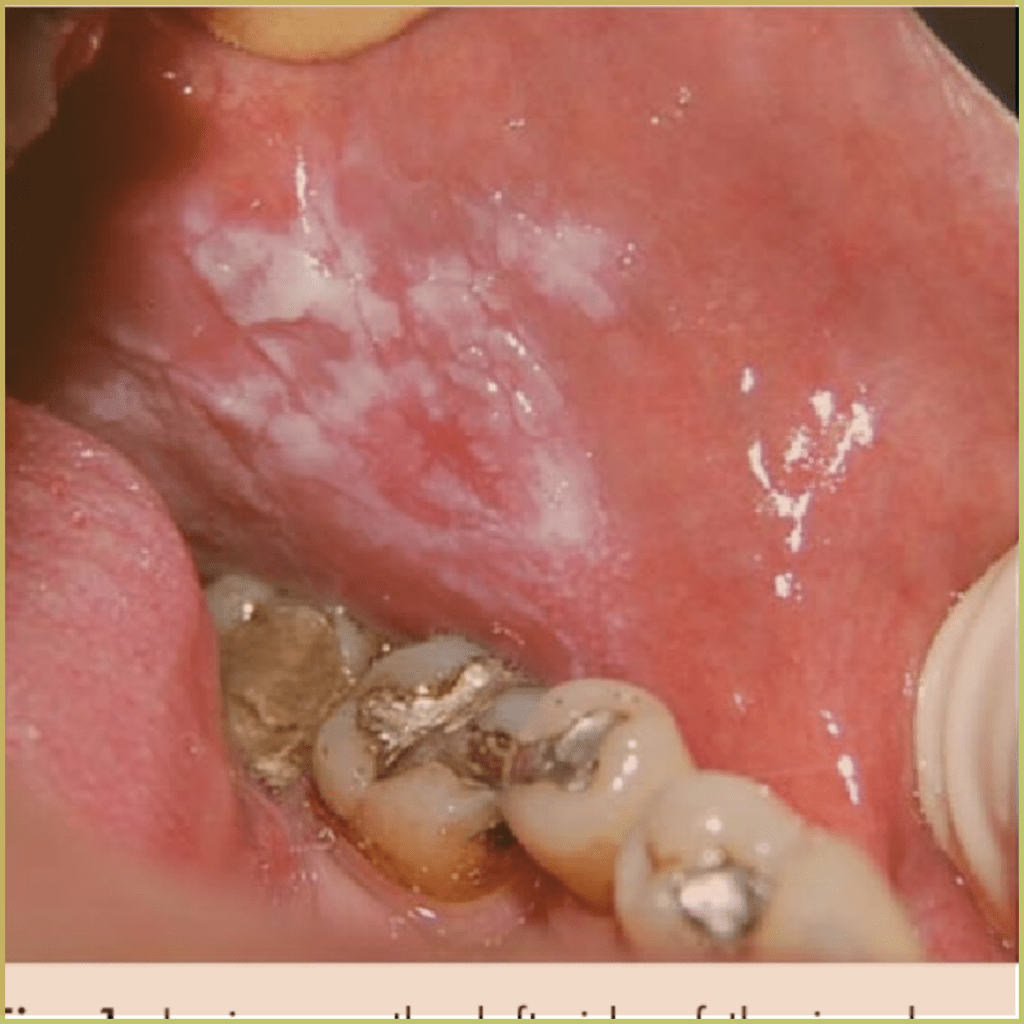

SMOKELESS TOBACCO KERATOSIS

Smokeless tobacco keratosis describes a keratotic change in the oral mucosa where smokeless tobacco products are placed. It is usually seen in the lower buccal vestibule or buccal mucosa (chewing tobacco). Irritant contact stomatitis can be caused by any chemical products used, including toothpastes, mouthwashes, and dental restorations. The common clinical presentation includes:

- Early lesion – filmy white to gray opalescent surface.

- Mature lesion – more keratotic white, fissured appearance and thickening of the epithelium.

Diagnosis is based on the lesion history, clinical presentation and microscopic findings, which may include:

- Hyperkeratosis with parakeratotic “chevron sign” on the surface.

- Increased vascularity.

- Hyalinization in submucosa and minor salivary glands.

- Epithelial dysplasia and carcinoma may be visible.

Your differential diagnosis should include:

- Idiopathic leukoplakia.

- Chemical or thermal burn.

- Frictional keratosis.

Treatment options include:

- Identification and elimination of predisposing factor(s).

- Excision or stripping of mucosal site if dysplasia present.

The prognosis is usually good if the patient stops the habit.